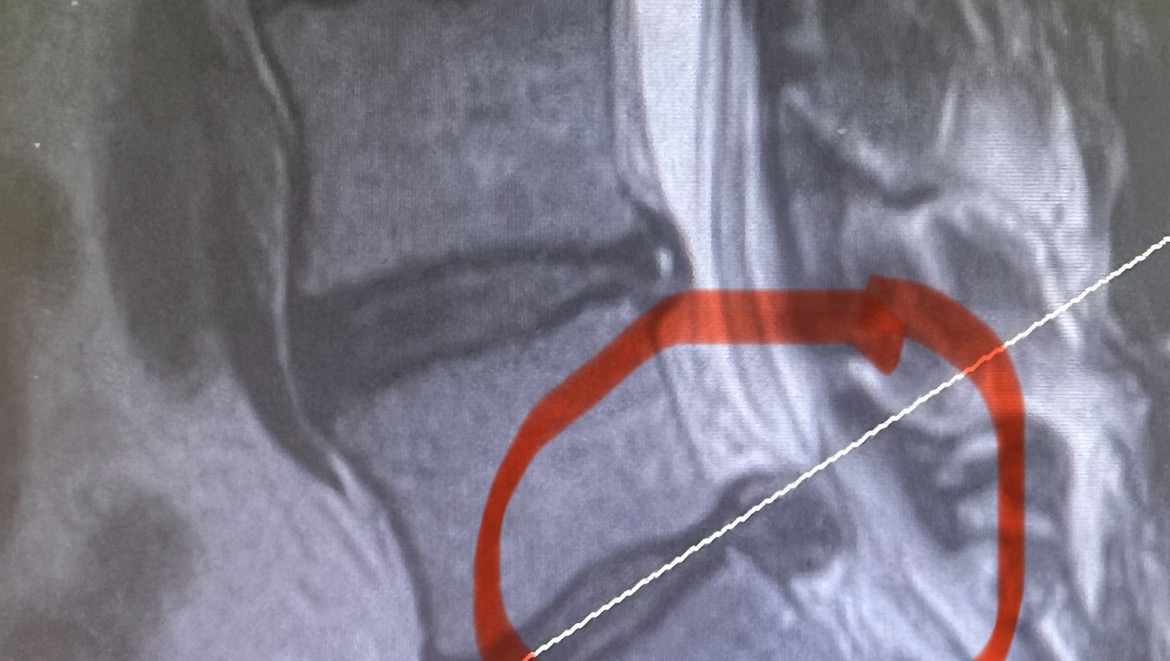

About a month ago I hurt my back. I have only missed one day of work and that was the day I went to the emergency room. I have 2 herniated discs one at L5 and one at S1. I have finally received a date for the surgery on January 25. This will be a full discectomy of my S1. Please pray before you give. I would rather pay you back the money then just ask you to donate so if that works please let me know. I also know this is the worst time to have money troubles. Thank you so much. I love all the well wishes and messages that everyone has sent me on Facebook.